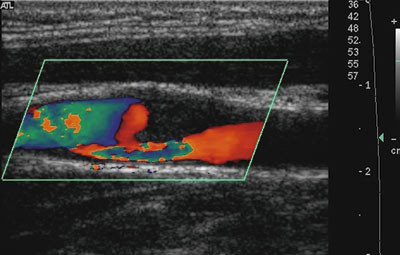

Lipidrike plakk har lav ultralydekkogenisitet, og det er vist at slike plakk representerer større klinisk risiko enn hva høyekkogene (kalkholdige) plakk gjør (32) (fig 4). En tynn fibrøs kappe øker muligheten for plakkruptur, og ultralyd kan i mange tilfeller vise tykkelsen av den fibrøse kappen. Det er også vist at asymptomatiske embolier fra en carotisarterie, påvist med transkranial ultralyd, predikerer senere cerebrovaskulære symptomer (33, 34).